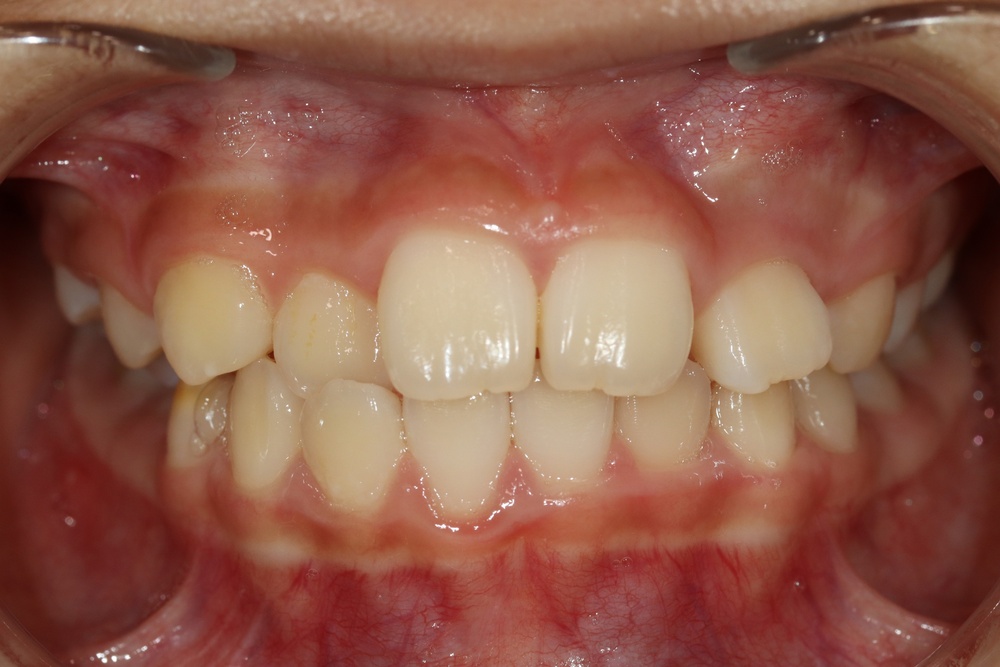

벌어진 부분을 레진으로 수복하여 틈이 없어졌습니다.

새로운 교정유지장치 철사도 부착해 드렸습니다.